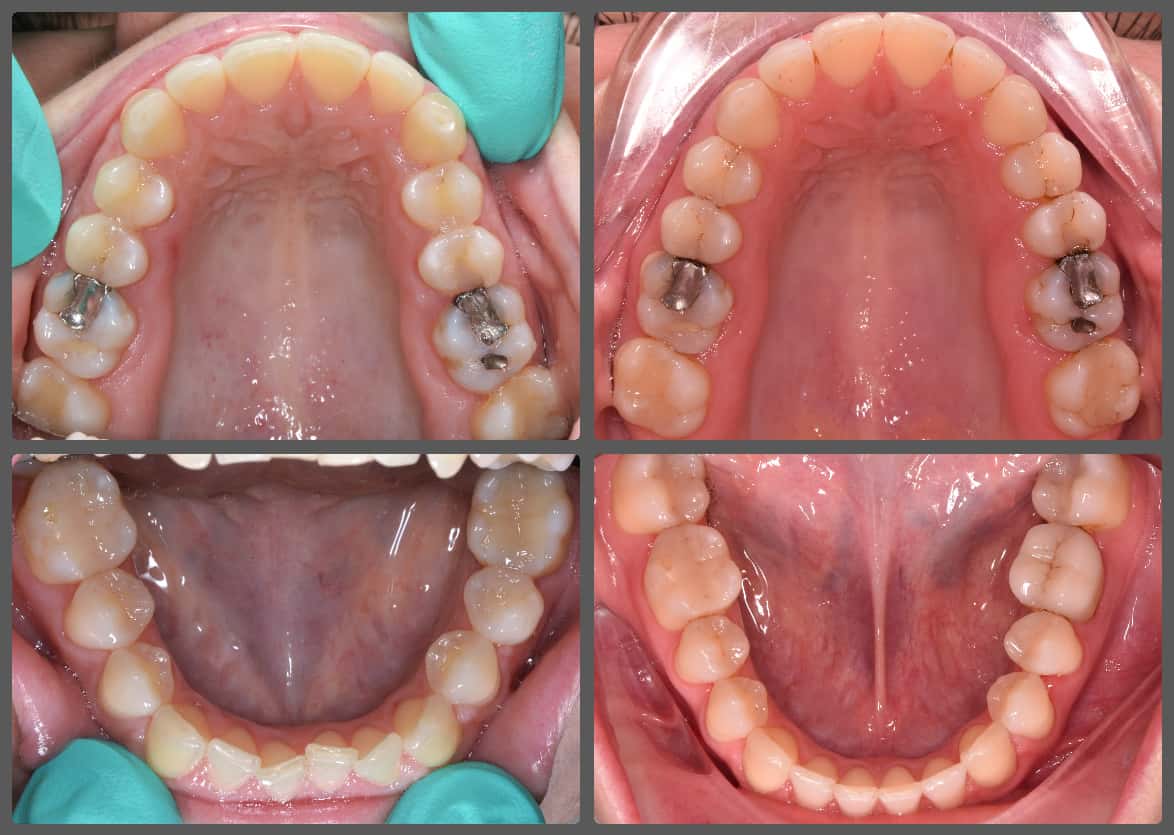

Petrát egy kollégám utalta be hozzám fogszabályozási konzultációra az erősen előrefelé dőlt alsó második őrlőfogai miatt. A fogak pozíciója miatt azok tisztítása nagyon nehéz volt, illetve fogászati ellátásuk is igen bonyodalmas. A bedőlt őrlőfogakon kívül enyhe mélyharapást, és enyhe alsó-felső torlódást diagnosztizáltam Petránál. Az eltéréseket Pitts21 rögzített fogszabályozó készülékkel, harapásemelőkkel és intermaxilláris gumihúzással korrigáltuk. A kezelés hossza 1 év 8 hónap volt. Petrának ez már a második fogszabályozó kezelése volt, és reméljük, hogy többre nem lesz szüksége. Ennek érdekében mindent megteszünk, az elért eredmény „rögzítésére” mélyhúzott retenciós sínt adtam Petrának, valamint a végállapotot digitális formában is rögzítettük, ezáltal a jövőben bármikor kérhető erre a szituációra egy új mélyhúzott retenciós sín.